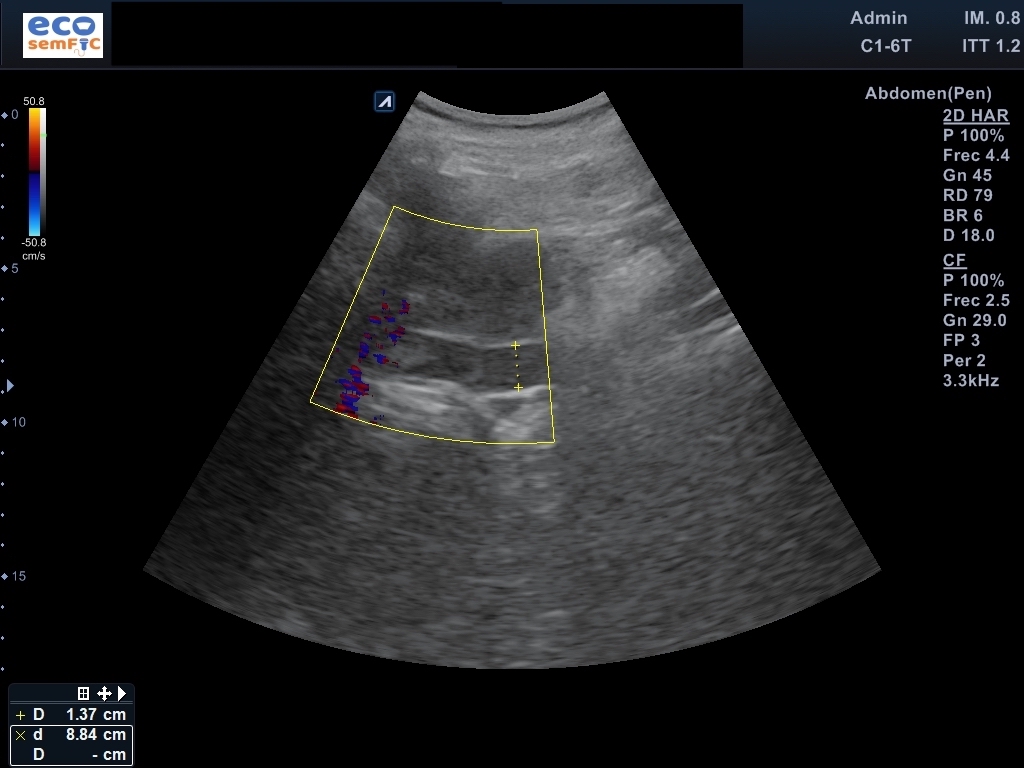

Limitada por poca colaboración, pero aceptable. En las áreas accesibles, hígado de superficie lisa y contorno regular, heterogéneo sin aparentes LOEs. Radicales intrahepáticos dependientes del conducto hepático derecho ectásicos. Colédoco proximal de 8,3 mm y distal de 14,3 mm a nivel de la cabeza del páncreas. Marco duodenal ocupado por contenido sólido aperistáltico en este momento. Páncreas visualizado en toda su extensión con Wirsung patente no dilatado, sin lesiones focales. Riñones de aspecto senil, conservan el grosor cortical y diferenciación parénquima-seno. Bazo homogéneo no aumentado ni lesiones parenquimatosas. Ausencia líquido libre o colecciones en áreas exploradas.